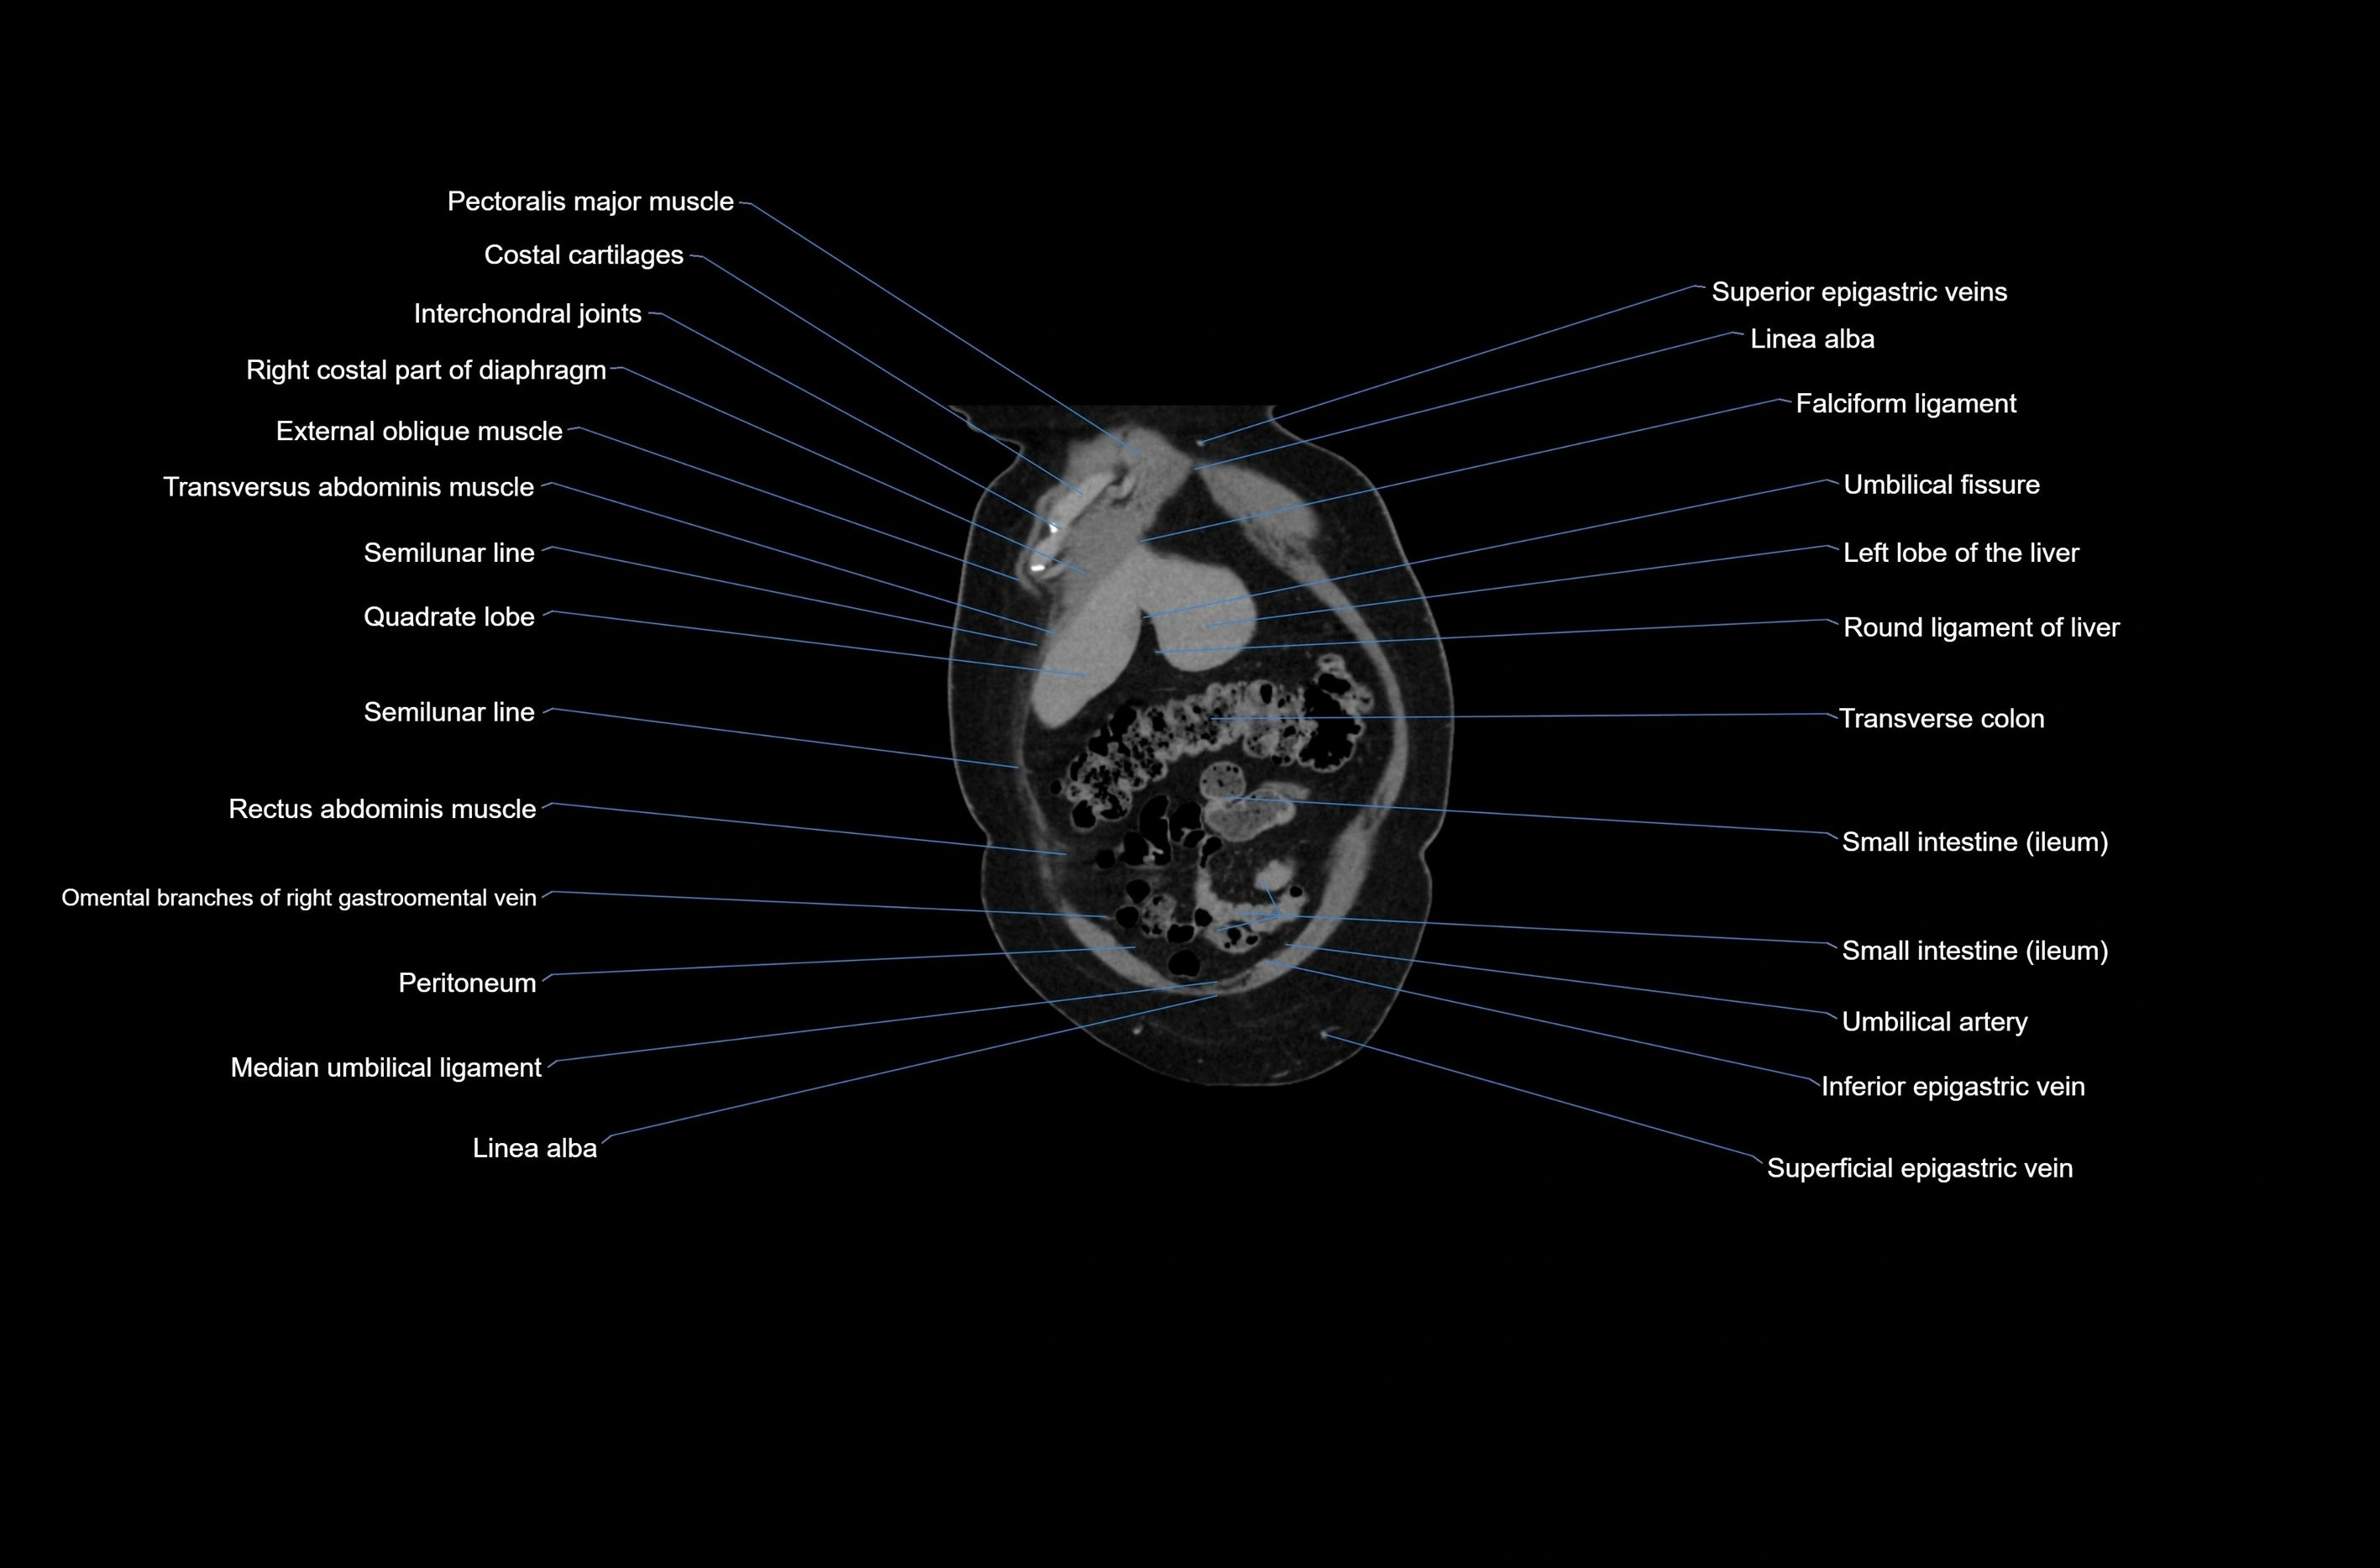

CT images